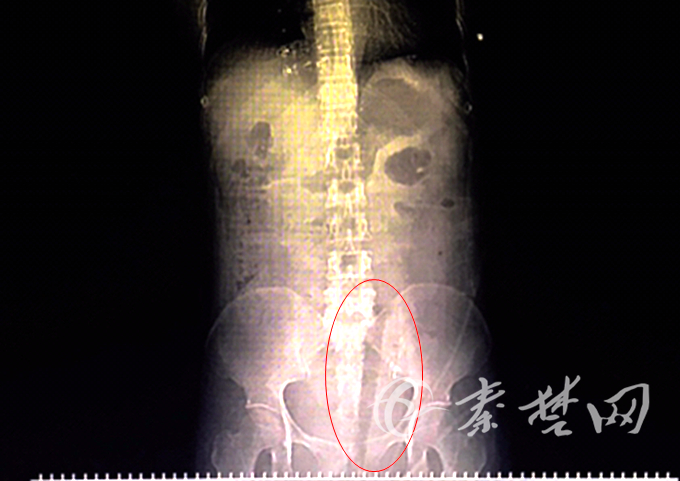

X光下,可见患者体内有异物(红圈所示)。

傍晚时分,陈女士被送达太和医院妇产中心,经紧急检查,断枝从其阴道口插入,并由阴道后壁贯穿而入,由左侧穹窿入盆腹腔。“腹腔镜探查发现,断枝穿透子宫向上贯穿至乙状结肠系膜,顶端插进腹腔十几厘米,到达髂脊水平,断枝末端在阴道外口,外部可见。”妇产中心副主任方彩云告诉记者。